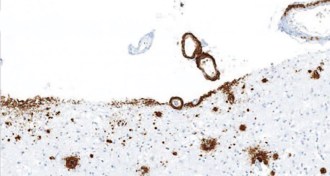

Mini microscope is a window into live muscle tissue

A tiny microscope offers unprecedented views of live human muscles.